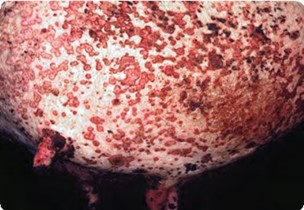

Apparition de nodules durs, arrondis et indolores (0,5 à 6 cm de diamètre), non adhérents. Préférentiellement ils se développent sur la tête (autour des yeux et du mufle), le cou et les membres). Il peut y avoir aussi des nodules sur les muqueuses et des atteintes mammaire avec un œdème prononcé.

: Lésions nodulaires sur un bovin malade (cliché J. M. Gourreau)